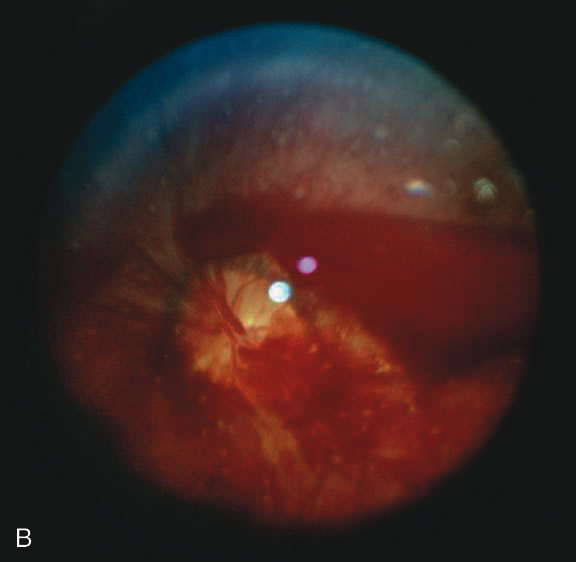

SHAKEN BABY SYNDROME The triad of the SBS includes brain injury usually with hemorrhage, ocular injury, and skeletal injury. These children often have no external signs of trauma. The infant and young child are particularly vulnerable because of their relatively large head, weak cervical musculature, large size of the cranial vault in relation to the size of the brain,3 and immature, unmyelinated brain. Violent shaking causes repetitive anteroposterior and side-to-side disorganized head movement with abrupt acceleration-deceleration forces.7,17,18,19 The magnitude of acceleration-deceleration forces needed to cause brain and eye injuries in humans is extreme but not exactly quantified.20 Although in Caffey's original description, he inferred that normal play activities could cause SBS-like injuries, we now recognize that this is not the case.21 Abusive head trauma is the most common type of child abuse resulting in death,22 although it represents only 3% to 5% of all cases referred to child abuse teams.23 Assault represents more than half of all traumatic brain injury in the first year of life and 90% of brain injuries between 1and 4 years of life. The average age of SBS victim is between 5 and 10 months,22–31 with most children younger than 2 years of age.22,25,26,30 Victims up to 5 years old are rare. The mortality rate of SBS, based on studies with more than 10 patients, is approximately 8% to 61%,23 although this may be a reflection, in part, of separation or imprisonment of perpetrators after the first incident. Recidivism rates are high. The most common perpetrators of SBS are biological fathers and biologically unrelated boyfriends of the mother.22,26,30,32,33 Babysitters, females 4.4 times more often than males,22 are the perpetrators in 4% to 20% of cases.22,26,33 Biological mothers commit this crime in 5% to 12% of cases.22,26,33 Only a minority (10% to 15%)23,33 of perpetrators confess, although it may be as high as 43%34 in fatal cases. SHAKEN BABY SYNDROME: SYSTEMIC MANIFESTATIONS Brain injury in SBS is common: Subdural hemorrhage is found in 10% to 93%, subarachnoid hemorrhage in 10% to 72%, posterior interhemispheric blood in 20% to 100%, stroke in 12% to 50%, intraparenchymal hemorrhage in 5% to 30% and parenchymal tears in 0 to 100%. 23,24,26,29,35 Increased intracranial pressure or cerebral edema is found in 44% to 85%.23,35 The wide variation in incidence figures reflects the nature of the study populations: findings at presentation, in survivors, or at autopsy. At autopsy, subdural hemorrhage, subarachnoid hemorrhage, and cerebral edema are the most consistent findings.21,34,36,37 Although one study using a mechanical model and autopsy investigation suggested that blunt head impact is required to generate the forces necessary to cause the brain injury of SBS,38 a wealth of clinical and pathologic investigations indicate that shaking alone can cause significant injury and even death. Perhaps calculation of forces does not allow for a full understanding as cellular and biochemical responses to shearing stress along with other factors such as anemia and hypoxia may play an important role that cannot be modeled. Violent shaking causes shearing forces that tear the bridging veins running from the cortex to the dural venous sinuses, resulting in subdural and subarachnoid hemorrhage. Shearing also causes diffuse axonal injury with secondary brain edema.39,40,41,42 The diagnosis of brain injury is usually confirmed with computed tomography (CT) scan. However, the CT scan may initially be normal or show edema without hemorrhage. Magnetic resonance imaging (MRI) may be useful to find hemorrhage not visualized on CT43 and to date the findings seen on CT. The long-term prognosis for children with brain injury secondary to SBS is poor. In one study, only 28% of survivors had normal neurologic exams on discharge from the hospital; this figure decreased to 8% to 14% in long-term studies.22 Late findings seen on imaging studies include cerebral atrophy, hydrocephalus ex vacuo, chronic subdural effusion, and encephalomalacia. Patients may have quadriplegia, diplegia, hemiplegia, mental retardation, developmental delay; learning disability, seizures (7% to 65%), and psychiatric/behavioral issues(28% to 50%).23,24,26,30,44 Skull fractures occur in 9% to 31% of shaken babies,23,30 with the parietal and occipital bones most affected. The characteristics of skull fractures that are highly suggestive of abuse include branching, stellate, crossing suture lines, multiple, greater than 5 mm wide, or progressively expanding fractures in a child less than 3 years of age.29 Rib fractures are the most common bone injury in SBS, and are usually posterolateral due to the perpetrator's hands grasping the child. Long bone fractures affect the tibia, forearm bones, femur, or humerus in decreasing order of prevalence. The characteristic metaphyseal fracture, which rarely occurs in young children except in the setting of abuse, results in a “corner” or “bucket handle” chip fracture at the end of the bone (Fig 9). Other injuries seen in SBS include hemorrhagic stripping of the periostium, spiral fractures, and nonsupracondylar humerus fractures—all due to shaking while the infant is held by an extremity, causing the long bones to be twisted and broken.29,30 SHAKEN BABY SYNDROME: OCULAR MANIFESTATATIONS Retinal Hemorrhages Retinal hemorrhage is the most common ocular manifestations of SBS. The incidence of retinal hemorrhages in SBS varies in published reports. This variation is in part due to methods of examination (ophthalmologists vs pediatricians, dilated vs undilated pupils) and the population studied. Overall, the incidence varies from 30% to 100%.18,21,30,38,51,52,53 The incidence in studies including children with abusive head trauma not due to shaking is lower than in studies only involving SBS. In postmortem studies, the incidence of retinal hemorrhages approaches 100%.34,51,54,55 Findings range from a normal fundus to a small number of scattered intraretinal hemorrhages in the posterior pole to massive, confluent hemorrhages from the posterior pole to the ora serrata.(Fig. 10) The hemorrhages may be subretinal, deep intraretinal (dot/blot), nerve fiber layer (flame shaped) or preretinal.19,45 Intraretinal hemorrhages are more common than preretinal or subretinal hemorrhages.32,46 Preretinal hemorrhages must be distinguished from traumatic retinoschisis (see later), which has particular diagnostic significance. White-centered retinal hemorrhages, although classically associated with endocarditis, can occur in any condition that causes retinal hemorrhages, including SBS. Vitreous hemorrhage may be small to massive, and may occur secondary to escape of blood from intraretinal collections or from torn vessels.19 Although vitreous hemorrhage may occur at the time of injury, it may also be a delayed finding occurring 1 to 3 days or more after the initial trauma.47,48 Retinal hemorrhages may be associated with papilledema in SBS. However, papilledema is seen in less than 10% of shaken babies.35, 49 These small, flame-shaped hemorrhages on and radiating around the optic nerve are not necessarily caused by shaking and may be seen in papilledema from any cause. However, retinal hemorrhages associated with SBS may be seen on the optic disc in the absence of papilledema.50 Retinal hemorrhage is usually bilateral but may also be asymmetric or unilateral. Retinal hemorrhage can not be dated with any precision and, therefore, should not be used to help determine when the abusive event occurred.46,47,56,57,58,59 At best, generalizations may be made with wide intervals. For example, intraretinal hemorrhages do not last months, and blood in schisis cavities does not go away in days. Retinal scars or optic atrophy do not form in days. The pathophysiologic mechanisms of retinal hemorrhage in SBS are varied. Vitreous and perhaps orbital shaking is likely to be involved in most of the vitreoretinal injuries. In children, the vitreous is well attached to the retina at the macula, blood vessels, and the periphery. Shaking of an infant causes the vitreous to shake, which, in turn, applies shearing forces to the retina at points of firm attachment. These shearing forces at the macula may split the retina at any layer, causing the formation of a cystic cavity, which may be filled partially or completely with blood (Fig. 11). This traumatic retinoschisis has been well documented in abuse cases by ultrasound, electroretinogram, and pathology.34,58,60,61,62,63,64 Histopathology reveals a widening of the retinal layers or a stripping of the internal limiting membrane. The vitreous may stay adherent or detach. Clinically, to recognize this important finding in SBS, the examiner may observe a hemorrhagic or hypopigmented curvilinear edge to the schisis cavity, with or without a fold in the retina (Figure 11).50,65,66 Recognition of this edge helps distinguish retinoschisis from subhyaloid hemorrhage. However, subhyaloid hemorrhage, which may have originated from blood breaking out of a schisis cavity, may obscure the underlying schisis. It is important to follow any potentially shaken child with preretinal blood in the macula until that blood has cleared as the signs of schisis may be unmasked as the blood resorbs thus confirming the diagnosis of SBS. The retinal fold or hypopigmented line may be a complete circle or just an arc. In the long term, these patients may have surprisingly few sequelae and good vision as the cavity flattens spontaneously. There may also be findings of permanent curvilinear, hypopigmented scars or retinal folds. These provide clues to prior abuse.67

There remain still other theories for retinal hemorrhage in SBS that also seem to play a minor role. Some have suggested a Purtscher-like mechanism due to an increase in intrathoracic pressure when the perpetrator squeezes the child's chest. Although the characteristic white retinal patches of Purtscher retinopathy may be seen in SBS (Fig. 11), there appears to be no correlation with rib fractures,35 and the finding is very uncommon. The failure to see significant retinal hemorrhaging after the chest compressions of cardiopulmonary resuscitation in both animal models and humans also argues against a Purtscher-like mechanism. Differential Diagnosis The differential diagnosis of retinal hemorrhages in a child is vast. However, if one considers a child with the full spectrum of injuries seen in SBS, including brain, skeletal, and eye findings, most would not dispute that the retinal findings are due to nonaccidental injury. However, in a child with a small number of retinal hemorrhages and without retinoschisis, (Fig. 10A) the diagnosis of SBS may be less clear. The birth process is likely the most common cause of retinal hemorrhages in newborns, varying in several reports from 11% to 31% or higher.4,15,78 These retinal hemorrhages are most common after vaginal or vacuum-assisted vaginal delivery.79–82 The exact mechanism is unknown, but there is no association with brain hemorrhages in these infants.79,81,83 Prostaglandin release may play an important role. The distribution of retinal hemorrhages secondary to the birth process may extend from the posterior pole to the ora serrata. Most often they are limited to dot, blot, or flame-type of hemorrhages but preretinal and less commonly subretinal hemorrhage may also be seen.79,81,84 Although macular hemorrhages are common,82,85 schisis has never been observed despite the examination of thousands of children. All types of retinal hemorrhages due to the birth process resolve by 6 weeks of age with the exception perhaps of deep foveal hemorrhage. The majority of hemorrhages clear much earlier. Most flame-shaped hemorrhages resolve by 3 to 5 days, with all resolved by 1 week.86,87 Any retinal hemorrhages seen beyond these dates should arouse suspicion of another cause. Retinal hemorrhages seen within the first 6 weeks of life may also be due to SBS, and additional investigations must be considered when appropriate. Caretakers often relate histories of relatively minor head trauma as the cause of injuries that are otherwise generating the suspicion of SBS.21,34 After much study, most authors88–90 conclude that severe injury after a minor fall should raise the suspicion that the history is false and that the child has been abused. Furthermore, “most investigators agree that trivial forces such as those involving routine play, infant swings, or falls from a low height are insufficient to cause” the injuries seen in SBS.21,91 Even severe accidental head injury such as depressed skull fracture or intracranial hemorrhage does not routinely cause retinal hemorrhages.90,92,93 In compiling the available literature, retinal hemorrhage occurs in less than 3% of accidental head trauma, and then, almost always only in cases of severe, life-threatening injury.35,53,72,91,92,94,95 In the few cases of accidental head trauma with retinal hemorrhage, the bleeding is confined to the posterior pole with dot-blot, flame-shaped, or preretinal hemorrhages. Occasionally, these hemorrhages can extend to the midperiphery. But even the most severe accidental head trauma injuries do not cause the extensive retinal hemorrhages seen in SBS, except perhaps when the injury mechanism involves multiple acceleration-deceleration events such a motor vehicle accident in which the car strikes several objects or rolls consecutively resulting in death of the child. Retinochisis has not been observed after accidental head trauma, although there is one case of a child who may have suffered a severe crush injury to the head (five skull fractures with brain extrusion) and also a few adults with other causes of injury who have been observed to have paramacular folds or subinternal limiting membrane hemorrhage. These cases should not be taken to imply that in the SBS age range, macular schisis has a differential diagnosis other than SBS. There are a variety of other causes of retinal hemorrhage in children (Table 5). However, these are usually easily identified on the basis of history, systemic physical examination, or ocular examination. The retinal hemorrhages are almost always few in number and confined to the posterior pole unless there is predisposing retinal pathology which causes the hemorrhages to be located elsewhere (e.g. at the active ridge in retinopathy of prematurity). If an examining ophthalmologist finds retinal hemorrhage in a patient with these systemic problems, the physician must also attempt to understand if the disease could be the cause of the hemorrhages or if the child has been abused.